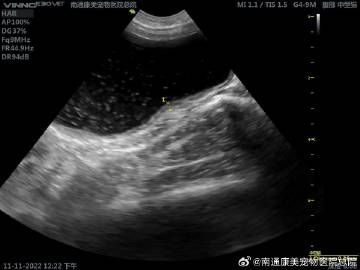

#南通康美# 膀胱炎在小动物泌尿系统疾病中临床上较为常见,通常以尿频、尿血、排尿异常为症状;通常以超声确诊,超声一般可见膀胱黏膜增厚,表面凹凸不平,膀胱内存在泥沙样沉淀物,可见强回声光点絮状物等;宠主若发现爱宠排尿异常,需及时就诊。